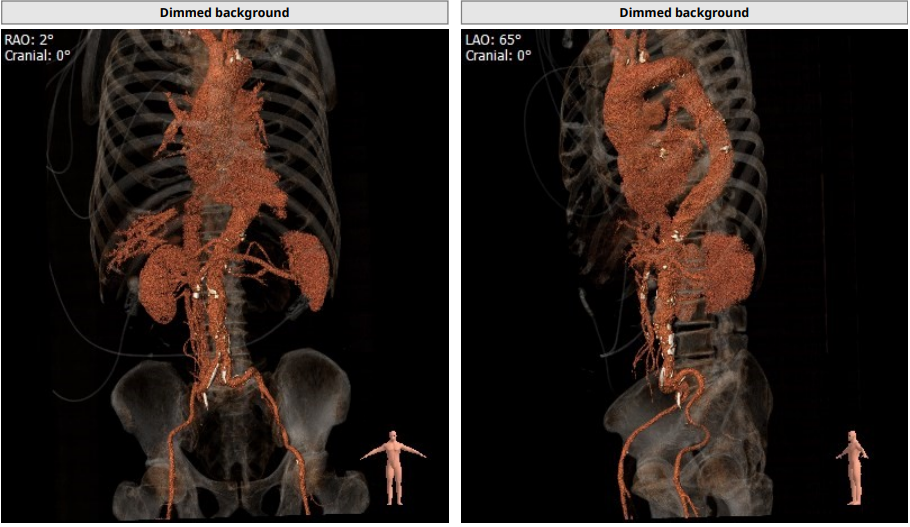

主动脉弓部走行尚可,降部有折角;髂股动脉有钙化分布,左右股动脉走行迂曲

入路情况:

主动脉弓部走行欠佳,主动脉弓部三根毛开口未见明显狭窄征象、未见发育变异,胸主动脉、腹主动脉走行迂曲、未见明显钙化斑块,管腔未见明显狭窄,双侧髂动脉-股动脉走形稍迂曲,管腔未见明显狭窄,综合考虑,推荐右侧股动脉做为主入路。右侧股动脉穿刺水平管腔直径约为 8.2 mm,右侧股动脉分叉约在股骨头下缘水平。